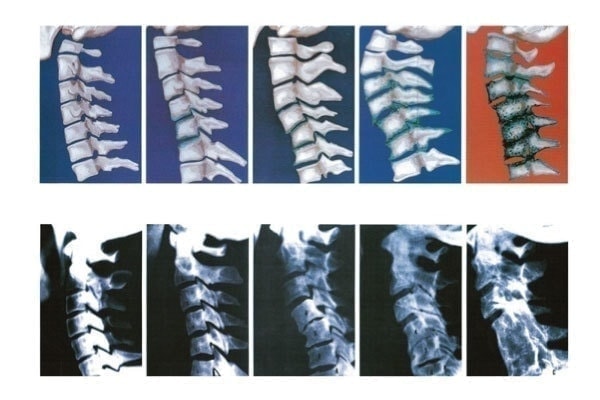

次の写真をご覧ください。

この写真では、頚椎の変性の様子を示しています。

椎間板周りの骨が、徐々に悪化している様子が分かります。

この変性の原因こそ、猫背やストレートネックによる、骨格のゆがみなのです。